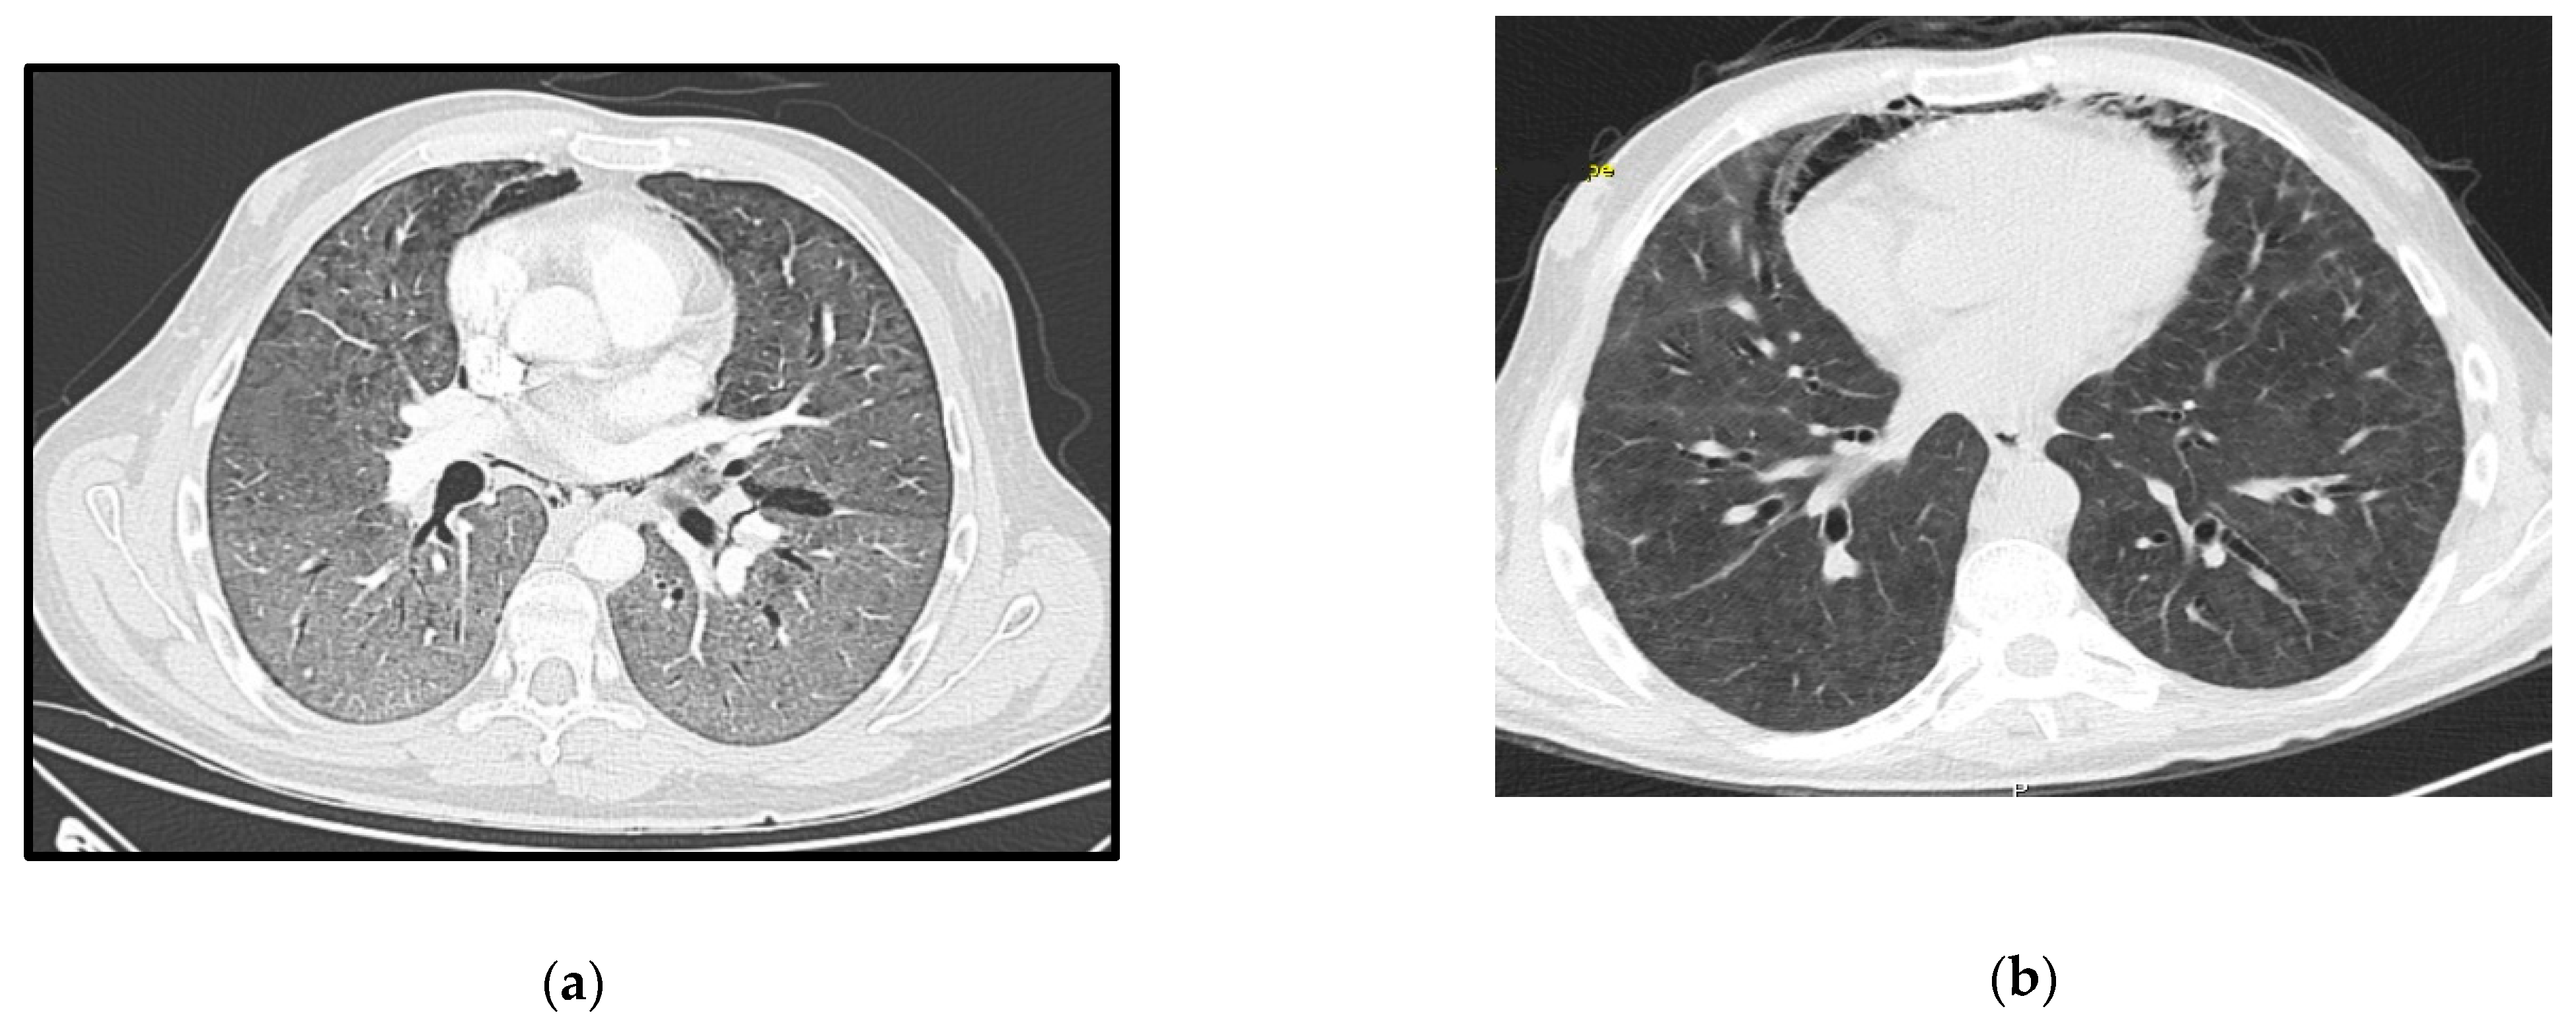

A 29-year-old male, HIV-positive since 2015, severely immunosuppressed that was lost to follow-up before starting ART. He presented in March 2019 at the emergency room (ER) with a one-day history of fever, shortness of breath and cough without providing information about his HIV status. Initial assessment showed polypnea of 30 cycles per minute (cpm), hypoxia, fever (39 °C), elevated C-Reactive Protein (CRP) and bilateral middle and lower zone air space opacities on chest X-ray. He was admitted to the ward and started empirical treatment for community acquired pneumonia (CAP). Two days later, he was transferred to the ICU with aggravated tachypnea (50 cpm), severe hypoxemia (paO2 49 mmHg) despite oxygen supplementation and pneumomediastinum, bilateral pneumothorax and diffuse ground-glass opacities on thoracic-CT scan (Figure 1a). The CD4+ lymphocyte count was 6/mm3 and the HIV-viral load was 18,200 copies/mL. All other microbiologic tests were negative. Treatment was then switched empirically to trimethoprim-sulfamethoxazole (TMP-SMX) 15 mg/kg of TMP each day in 3 takes plus corticosteroids for a presumed diagnosis of PJP. Later the diagnosis was confirmed by positive immunofluorescence as Pneumocystis jirovecii (P. jirovecii) in bronchoalveolar fluid (BAL).

Figure 1.

Case 1 thoracic CT-scan at diagnosis (a) and follow-up (b).

Due to refractory hypoxemia and given the high probability of barotrauma, the patient was started on venovenous-ECMO(VV-ECMO) without prior tracheal intubation. He later needed intubation due to poor bronchial clearance of secretions and completed a 14 days-period of protective IMV in an attempt to reduce extra corporeal support. He completed 21 days of therapy with TMP-SMX plus corticosteroids according to recommended PJP treatment dosage (prednisolone 40 mg two times day for 5 days, then 40 mg each day for 5 days and after that 20 mg each day for 11 days). ART was started 15 days after the ICU admission, with a significant reduction in the viral load one month later (151 copies/mL). ECMO and protective IMV were maintained for 40 days, followed by 19 days of weaning off. The pneumomediastinum and bilateral pneumothorax were managed conservatively, and a new CT-scan performed 50 days later showed great improvement (Figure 1b). He was transferred to the ward after 69 days of ICU stay showing signs of significant myopathy. Three months after discharge, he was revaluated at outpatient care as fully recovered and with CD4+ lymphocyte count improvement (49/mm3).